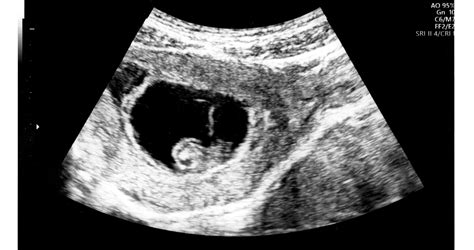

A magzati szív-ultrahangvizsgálat (más néven magzati echokardiográfia) egy speciális ultrahangvizsgálat, amelynek célja a magzati szív anatómiájának és működésének részletes értékelése. E vizsgálat segítségével már méhen belül kiszűrhetők a komplex, összetett szívfejlődési rendellenességek.

A magzati echokardiográfia kifejezetten a veleszületett szívhibák kiszűrését célozza. Ennek során ellenőrizni tudjuk a szív anatómiáját, a szívbillentyűk, szívizomzat funkcióját, áramlást és szívfrekvenciát tudunk mérni, így a szívfejlődési rendellenességek és szívritmuszavarok döntő hányadára már magzati korban fény derülhet.

A vizsgálat során részletes képet kapunk a magzati szív anatómiájáról, beleértve a kamrákat, a pitvarokat, a szívbillentyűket és az erek rendszerét. Lehetővé teszi a magzati szív működésének követését, például a szívritmus, a szívverések számának és erősségének értékelését. Segítségével azonosíthatók a szívrendszeri rendellenességek vagy szívfejlődési rendellenességek, például szívbillentyű problémák, septum-rendellenességek (szívfal rendellenességek), vagy egyéb szívhibák. Emellett a szakember megvizsgálja a magzati szív szállító artériáit, például a bal és a jobb aortát.

A magzati szív szűrés szempontjából az egyik legbonyolultabb szerv, vizsgálatához a legmodernebb ultrahangkészülék, valamint igen alapos gyermekkardiológiai ismeret és gyakorlat elengedhetetlen. A vizsgálatot a hasfalon keresztül, egy speciálisan a szív vizsgálatára kifejlesztett ultrahangvizsgáló fejjel végezzük. Több metszési síkból tulajdonképpen 3D-ben rekonstruáljuk a szívet, így az összetett szívhibák döntő hányada felismerhető.

A magzati szívultrahang vizsgálatra általában a várandósság 19. és 21. hete között kerül sor. Az ultrahang technológia fejlődése ma már lehetővé teszi, hogy egyes súlyos szívfejlődési rendellenességek már 12 hetes korban kiszűrhetők legyenek. A 12 hetes szűrést követően azonban mindenképpen szükséges további echokardiográfiás vizsgálat a 19-21. héten.